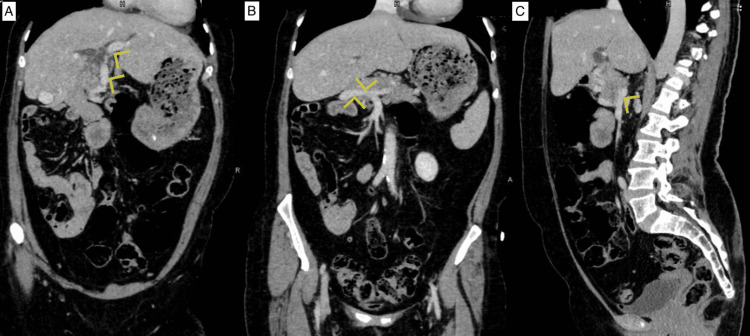

A 60-year-old female, with a history of laparoscopic cholecystectomy in 1996, which was converted to an open approach due to bleeding from an unidentified vessel, was referred to our practice for surgical management of a common bile duct stone that was not amenable to endoscopic retrograde cholangiopancreatography (ERCP). An abdominal computed tomography (CT) scan was obtained at our facilities to better delineate the patient’s biliary anatomy. The CT scan revealed multiple incidental findings of intestinal malrotation, a left-sided inferior vena cava (IVC), azygous continuation of the IVC, and a double portal system, characterized by the presence of two distinct portal veins entering the liver. In this scan, the superior mesenteric vein was seen giving a branch anterior to the pancreas before joining the splenic vein behind the pancreas (Figure 1).

This anterior branch continues towards the porta hepatis as a portal vein, and the posterior branch joined by the splenic vein continues laterally to the right and enters the liver at its edge close to segment VI as the second portal vein (Figure 2). The two portal veins were noted to communicate inside the liver parenchyma near segment VIII (Figure 3).